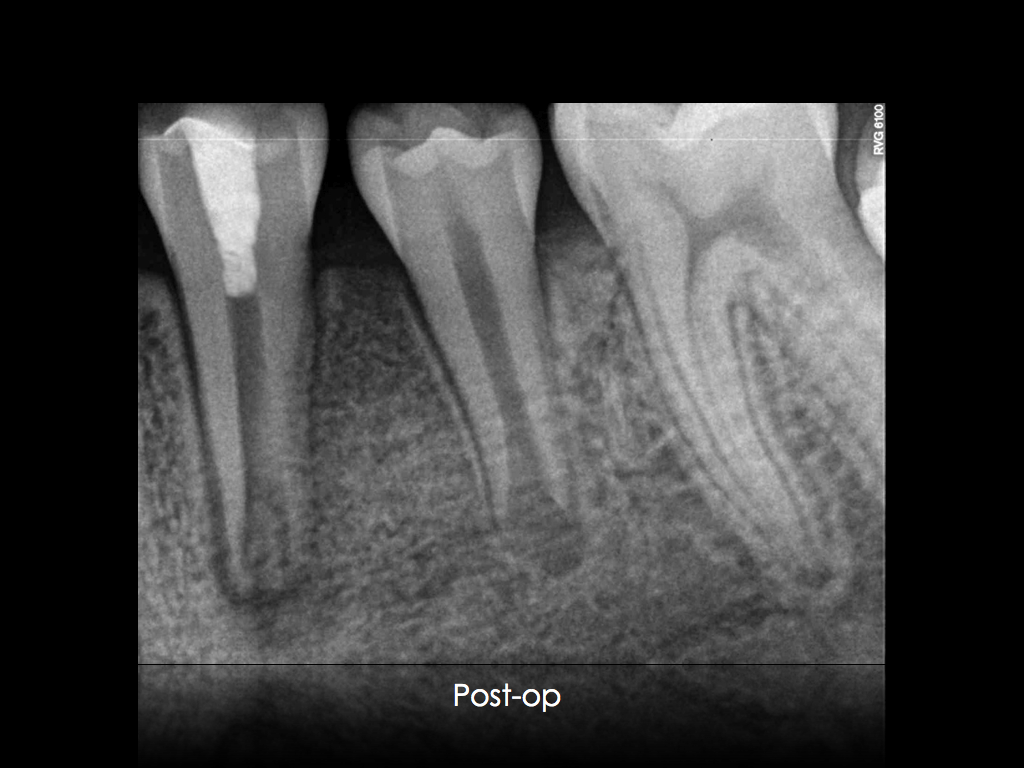

Anbei die Bilder und Röntgenaufnahmen

In diesem Fall wurde durch eine Stiftinsertion bereits sehr viel Wurzeldentin distal geopfert.Deshalb haben wir uns hier für eine intrakanläre Strahlung mit AlO entschieden. Voraussetzung dafür ist allerdings ein verschlossener Wurzelkanal. Die Gefahr eines Emphysems und/oder des Transports von Strahlungspartikeln mit Debris und Smearlayer nach periapikal muß ausgeschlossen sein. Deshalb kann in so einem Fall erst nach der Wurzelfüllung die Vorbereitung der Oberfläche erfolgen

Danach erfolgt das übliche Ätzen, Silanisieren der angrenzenden Kunststoffflächen und Bonden ( bei uns Optibond FL ). Wir haben Ever XFlow Bulk appliziert und mit einem Microbrush (klein, weiß) adaptiert.

Anschließend wurde mit der Valo und dem Endoaufsatz 2x 20 Sekunden polymerisiert.

Die Glasfaserstifte wurde danach mit Rebilda als dualhärtendes Material geklebt.